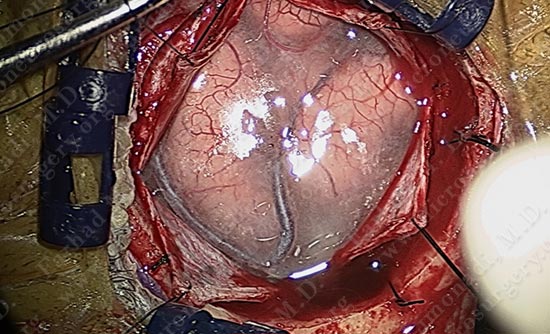

While patient is awake and conversing with Dr. Limonadi, motor cortex stimulation was utilized to locate the motor cortex.

Motor cortex was identified and is colored green. The tumor is deep and within the parenchyma of this gyrus.